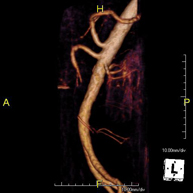

Prueba diagnóstica no invasiva que consiste en la obtención de imágenes de alta definición anatómica de todo el cuerpo mediante el empleo de un campo electromagnético y ondas de radio (con un emisor y un receptor). No utiliza radiación ionizante. Es una prueba muy importante en la búsqueda de metástasis en pacientes con neoplasia conocida. No requiere preparación previa. No es necesario el empleo de contraste paramagnético (Gadolinio). - Angio-RM Aorta abdominal

Prueba diagnóstica no invasiva que consiste en el estudio de la arteria aorta abdominal, obteniendo imágenes de alta definición anatómica mediante el empleo de un campo electromagnético y ondas de radio (con un emisor y un receptor). Es indispensable el uso de contraste paramagnético (Gadolinio). Sin embargo, no utiliza radiación ionizante. La calidad de las imágenes permite realizar reconstrucciones en 2D y 3D. Está indicado en aquellos pacientes con enfermedad vascular (aterosclerosis), estudio de aneurismas, en estudios pre-quirúrgicos de lesiones adyacentes a la aorta abdominal como "mapa" vascular, etc. - Angio RM Aorta-ilíaca

Prueba diagnóstica no invasiva que consiste en el estudio de la arteria aorta abdominal de las arterias ilíacas, obteniendo imágenes de alta definición anatómica mediante el empleo de un campo electromagnético y ondas de radio (con un emisor y un receptor). Es indispensable el uso de contraste paramagnético (Gadolinio). Sin embargo, no utiliza radiación ionizante. La calidad de las imágenes permite realizar reconstrucciones en 2D y 3D. Esta prueba está especialmente indicada como estudio pre-quirúrgico (mapa vascular) antes de intervenciones percutáneas o quirúrgicas de aorta abdominal y arterias ilíacas, estudio complementario en pacientes con isquemia de miembros inferiores, etc. - Angio RM Arterial extremidades inferiores